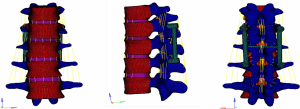

The three-dimensional entity model of T11–L3 and the screw-rod system were constructed using SolidWorks (Figures 7-9).

Meshing and supplemental establishment of the intervertebral disc and ligament: the three-dimensional entity models of T11–L3 and screw-rod system established in SolidWorks were imported into HyperMesh. Using the powerful mesh-making and dissection function of HyperMesh, a tetrahedral mesh was generated for the assembly, and 1-mm-thick cortical bone was constructed at the same time. The mesh sizes were 2 mm for T11–3 and 1 mm for the screw-rod system. Then, the structures of the endplate, annulus fibrosus, nucleus pulposus, anterior longitudinal ligament, posterior longitudinal ligament, intertransverse ligament, supraspinous ligament, interspinous ligament, ligamentum flavum, joint capsule ligament, and superior and inferior articular process cartilage were supplemented according to the anatomical site and shape to obtain a three-dimensional finite element model of T11–L3, which consisted of 191,386 elements and 55,741 nodes (the nodes and elements of T11–L3 Model Figure 10).

A three-dimensional finite element model of T11–L3 with the screw-rod system was obtained after the screw-rod system was added; it consisted of 310,970 elements and 73,469 nodes (the nodes and elements of T11–L3 Model with Pedicle Screw System Figure 11).